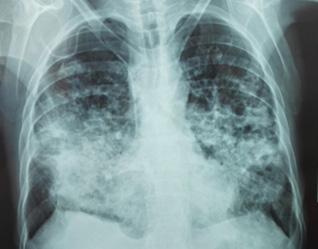

Radiología:

Cardiomegalia

Signos de congestión pulmonar.

Radiografía: cardiomegalia con hipertensión venosa pulmonar